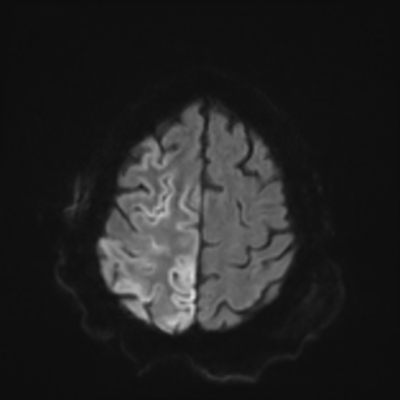

You come back the next day and see how things are going. The patient's electrographic record has shown a moderate encephalopathy (diffuse slowing, disorganization) with frequent right posterior quadrant delta slowing. Based on this result, and an adequately improved clinical examination, you give the okay to proceed with obtaining an MRI of his brain. This is shown below.

MRI brain (DWI)